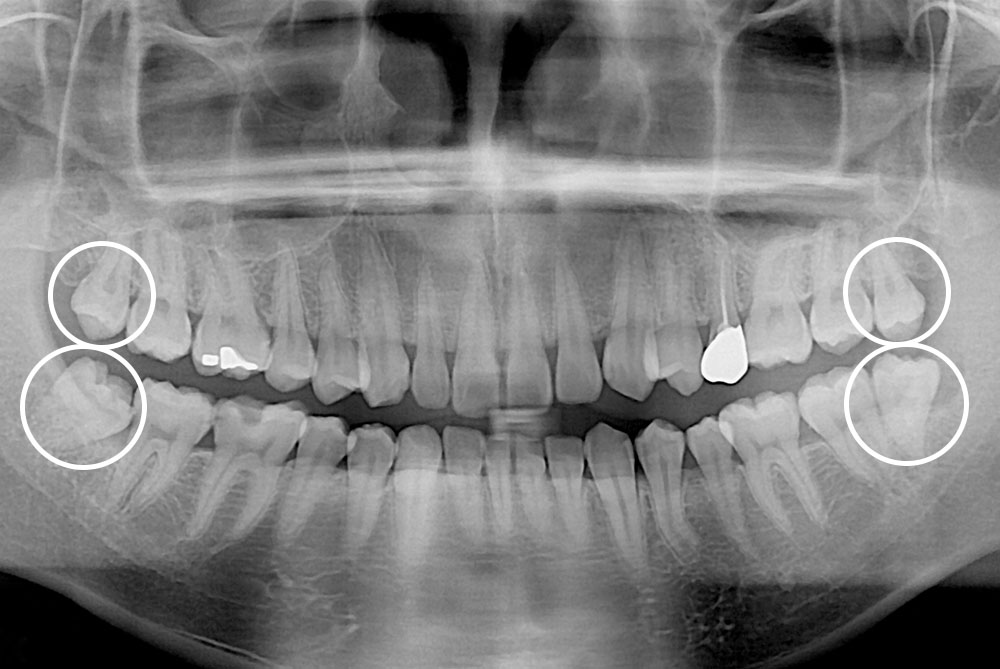

[사랑니] 매복 사랑니 발치

치료후 : 2019-02-13

세종치과는 구강악안면외과학 박사이신 원장님이 발치하는 치과입니다.